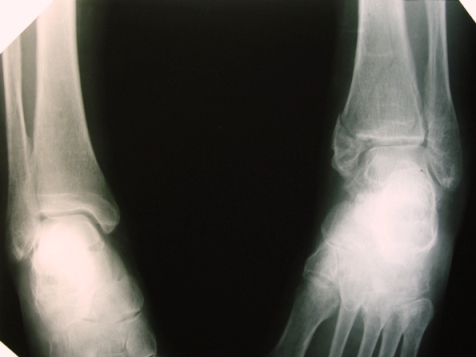

Посмотрели  снимки  после репозиции - не понравилась зона синдесмоза.

Сделали  3/4-е  -  впечатление,  что  в  99-том  там  что-то было. На

5.11.09г. запланирована КТ.

Имя     : Косая  после репозиции.JPG